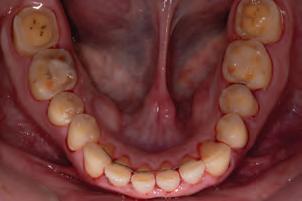

A 77-year-old Caucasian patient presented to the dental clinic after five years without dental care. The clinical findings showed significant bone loss, chronic periodontitis, and loss of some teeth that stabilized the occlusion. The patient reported cold sensitivity in tooth #46, especially when ingesting liquids.

Periapical X-ray confirmed the findings of the clinical examination and root caries was also detected in the distal root of tooth #46, which answered positively to the sensitivity test (Fig.1-2).

The treatment plan began with a focus on returning the patient to adequate periodontal health. In a subsequent session, with improved condition of the periodontium, the restoration of tooth #46 was performed. Under block anesthesia of right inferior alveolar nerve and rubber dam isolation, the amalgam restoration was completely removed and access to the caries cavity obtained (Fig. 3-5). Despite the proximity to the pulp tissue, no exposure occurred, and the class II cavity was fully restored with Biodentine™ (Fig. 6-8).

At two months’ follow-up, no symptoms were reported, no periapical lesion was observed radiographically, and the clinical examination showed normal vitality (Fig. 9-10). Thus, it was decided to perform the definitive restoration, leaving Biodentine™ as the definitive base.

With regard to the periodontium, the subgingival treatment had the desired effect within two months. The occlusal adjustment allowed for a decrease in the mobility of two teeth that had previously displayed increased mobility due to vertical bone loss.